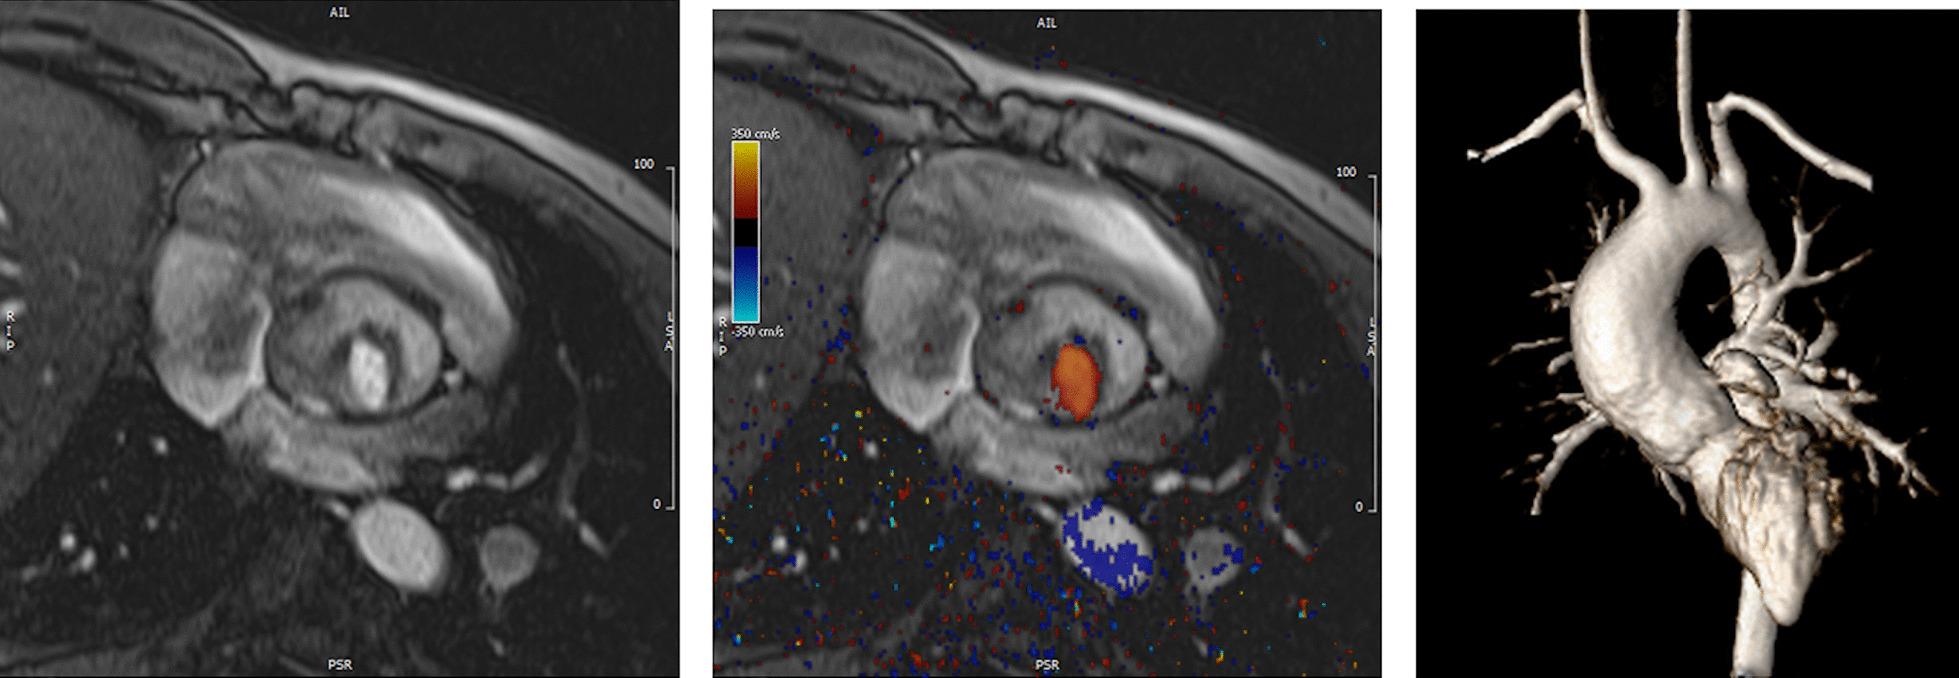

Cardiovascular magnetic resonance (CMR) has been utilized in the management and care of pediatric patients for nearly 40 years. It has evolved to become an invaluable tool in the assessment of the littlest of hearts for diagnosis, pre-interventional management and follow-up care. Although mentioned in a number of consensus and guidelines documents, an up-to-date, large, stand-alone guidance work for the use of CMR in pediatric congenital 36 and acquired 35 heart disease endorsed by numerous Societies involved in the care of these children is lacking. This guidelines document outlines the use of CMR in this patient population for a significant number of heart lesions in this age group and although admittedly, is not an exhaustive treatment, it does deal with an expansive list of many common clinical issues encountered in daily practice.

心血管磁共振(CMR)在儿科患者的管理和护理中已经应用了近 40 年。它已经发展成为评估最小的心脏的宝贵工具,用于诊断、介入前管理和随访。尽管在许多共识和指南文件中提到,但在儿科先天性心脏病和后天性心脏病领域,目前还缺乏一份由众多参与儿童护理的学会共同认可的、最新的、独立的、针对 CMR 使用的大型指南。本指南文件概述了 CMR 在该年龄段的许多心脏病变中的应用,尽管不能说是详尽的治疗方法,但它确实涉及了在日常实践中经常遇到的许多常见临床问题的广泛列表。